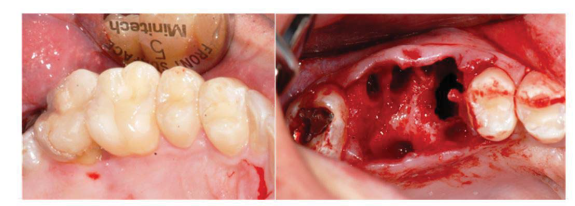

A 33-year-old man reported an episode of bleeding in the mouth and extravasation of fluid through the nose during liquid ingestion. The bleeding occurred in the upper right first molar region over one year, and there was extravasation of blood and serous fluid through the nose associated with pain and pressure on the same side of the face, when the patient was yawning. The medical condition did not show any comorbidity. In the intraoral exam, a 7mm periodontal pocket was detected. A gingival recession was also observed around the UFM and a Valsalva test was negative. The panoramic x-ray showed vertical bone loss in the super right first and second molar (URFSM) region. There was a bilateral alveolar ex-tension of maxillary sinus with opacification on the right maxillary sinus only (figure 2). We prescribed a CBCT exam, which showed severe furcation in-jury, external root reabsorption and vertical bone loss around cortical floor, and a thickening of the sinus mucosa around the URFSM. There was a rupture in the floor of the cortical sinus (figure 3). The diagnostic hypothesis was OMS related to periodontal disease or maxillary sinus tumor of the maxillary sinus floor. The extraction of the URFSM was done with curettage of the soft tissue associated with dental roots. In the surgical procedure, a 1cm diameter oroantral communication was observed, treated with intra alveolar fibrin sponge covered with a vestibular flap of oral mucosa (figure 4). The microscopic analysis showed no signs of malignancy and chronic inflammatory cell infiltrate compatible with inflammatory periodontal disease (figure 5). The final diagnosis was odontogenic maxillary sinusitis related to periodontal disease. A corticosteroid nasal spray was prescribed, and three months after the surgical procedure no clinical signs or symptoms were observed. A new panoramic x-ray six months after the surgical procedure showed normal radiopacity of the right maxillary sinus (figure 6).